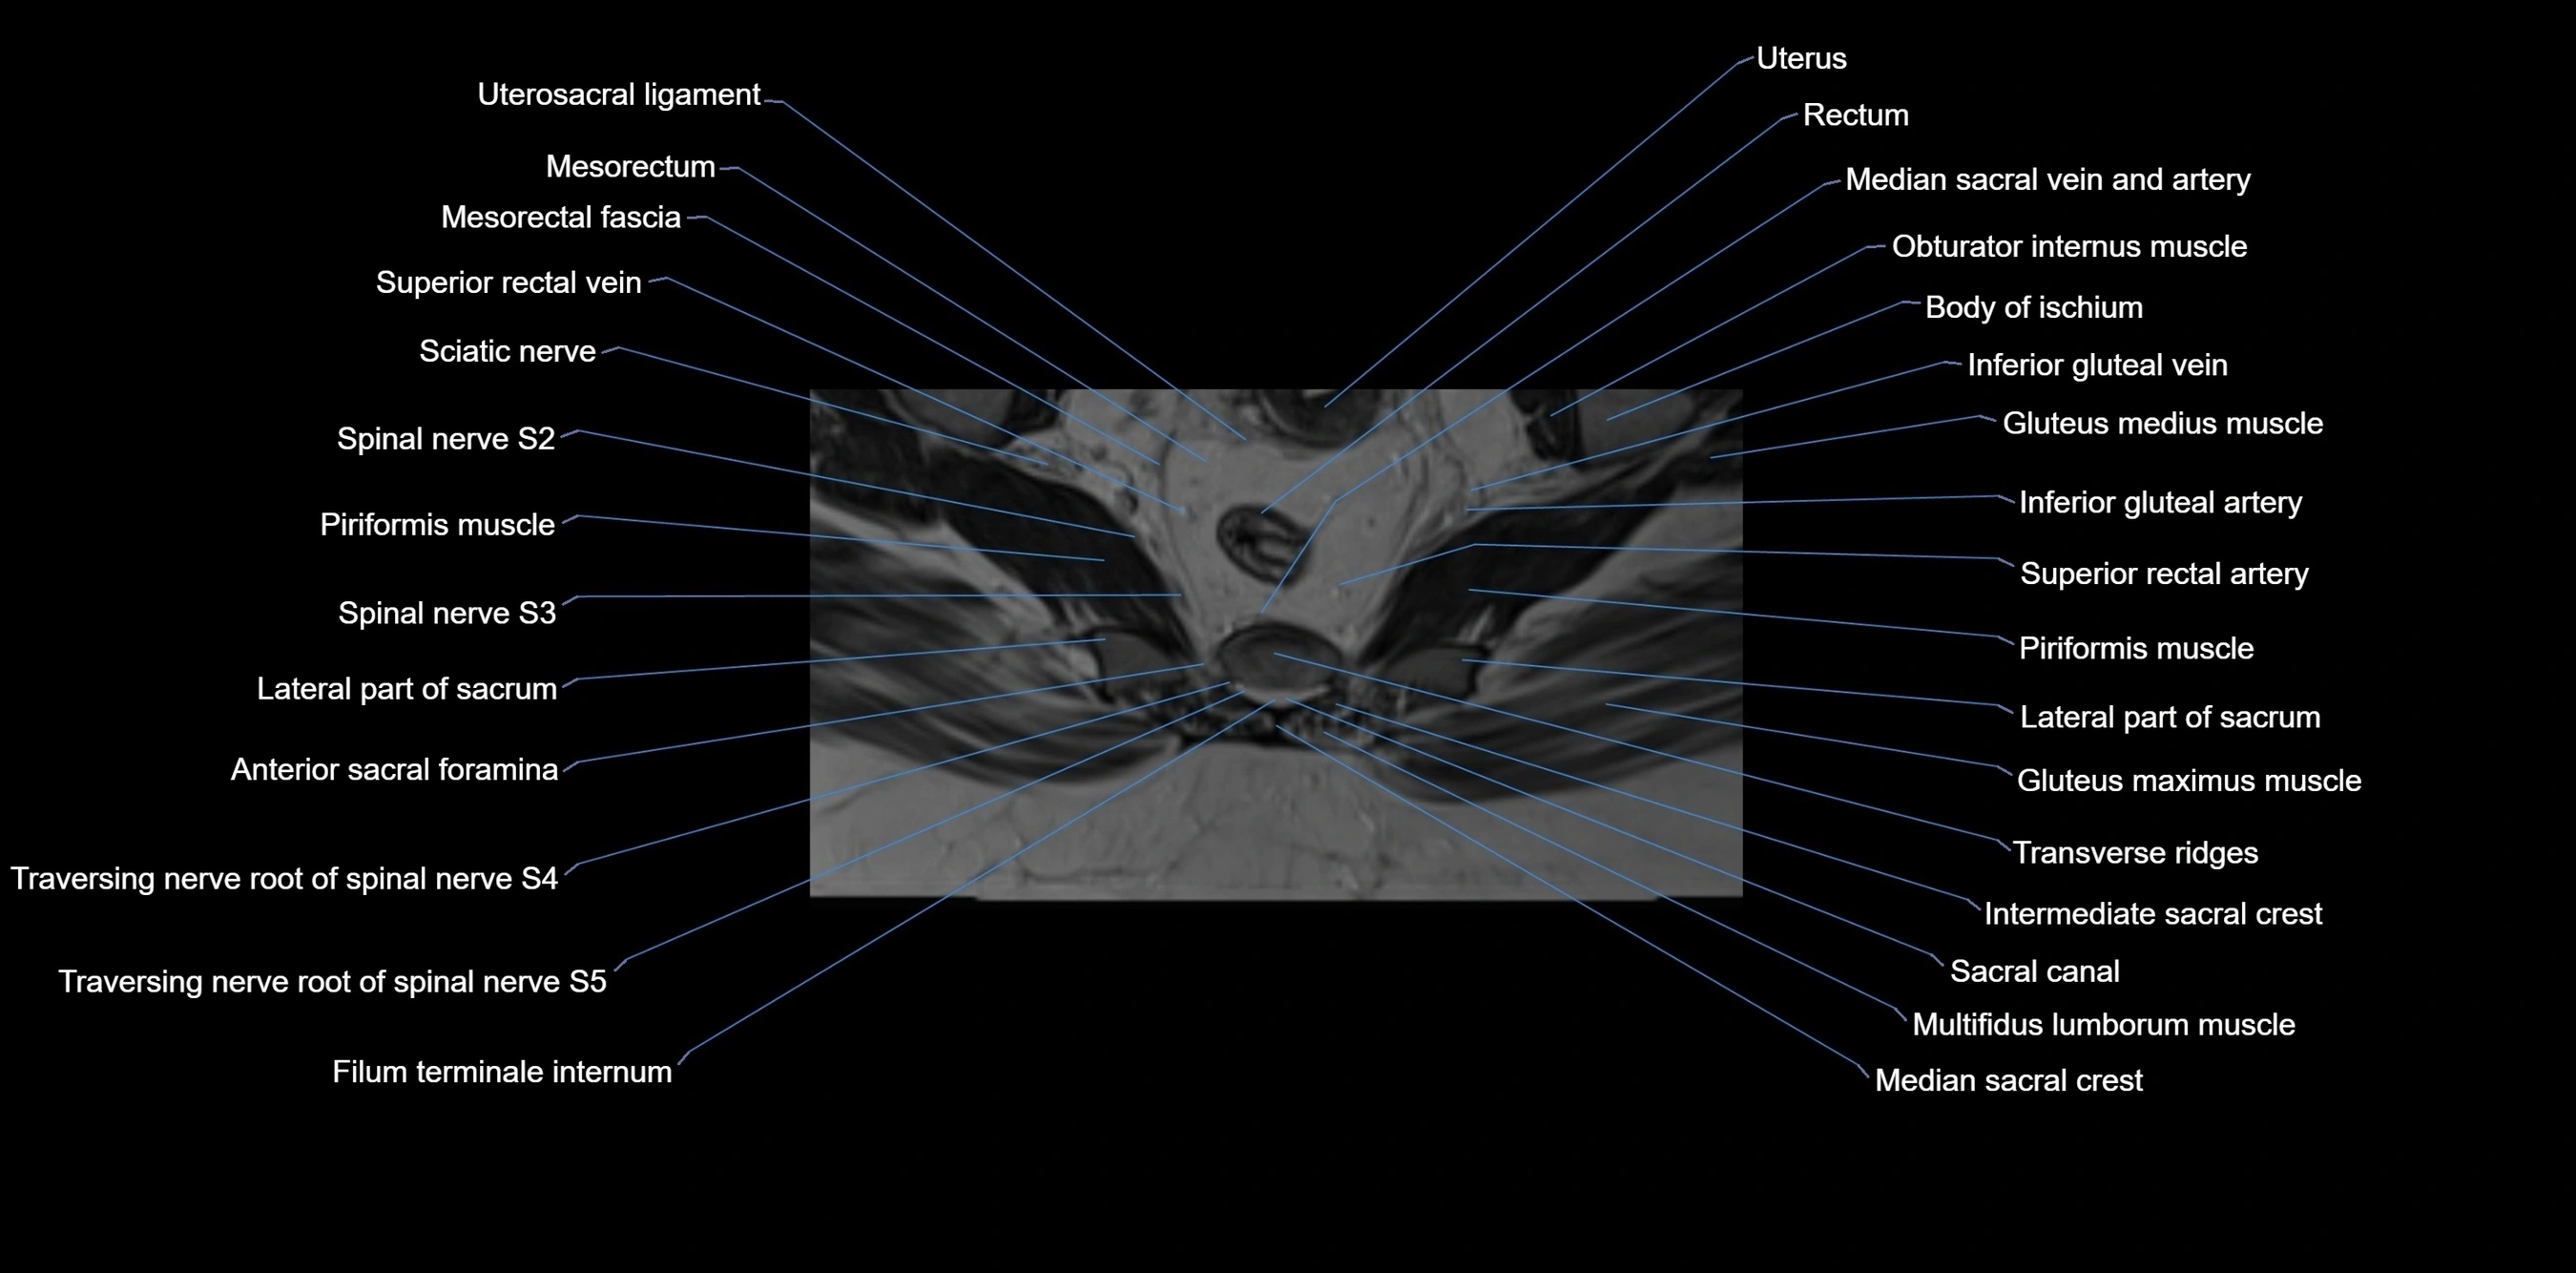

MRI image

image